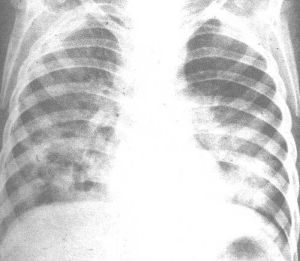

(一)X線胸片,肺部有炎性浸潤陰影(應避免搬動宜床旁拍片)。(二)病原學檢查:應儘快做痰塗片和培養,明確致病菌。